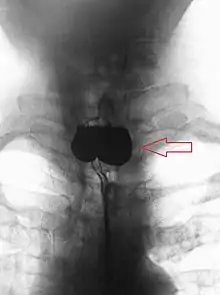

AP X-ray of a Zenker's diverticulum

A combination of the simple barium swallow and a thorough endoscopy will normally confirm the diverticulum.[4]